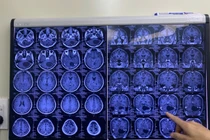

Qua thăm khám và kết quả cận lâm sàng phát hiện tình trạng tăng áp lực nội sọ và liệt mặt do khối u lớn vùng góc cầu tiểu não bên phải chèn ép các dây thần kinh gây giãn não thất phía trên.

Kết quả chụp cộng hưởng từ kiểm tra cho thấy tình trạng giãn não thất cải thiện rõ rệt sau mổ, điều này có nghĩa là tăng áp lực nội sọ là do chính bản thân khối u phát triển kích thước quá lớn.

Cân nhắc tuổi thai lúc này đã được 32 tuần và nguy cơ khối u chèn ép gây tụt kẹt não, các bác sĩ đã hội chẩn liên chuyên khoa và đưa ra chỉ định mổ lấy thai chủ động rồi mổ lấy u não sau đó 2 ngày.